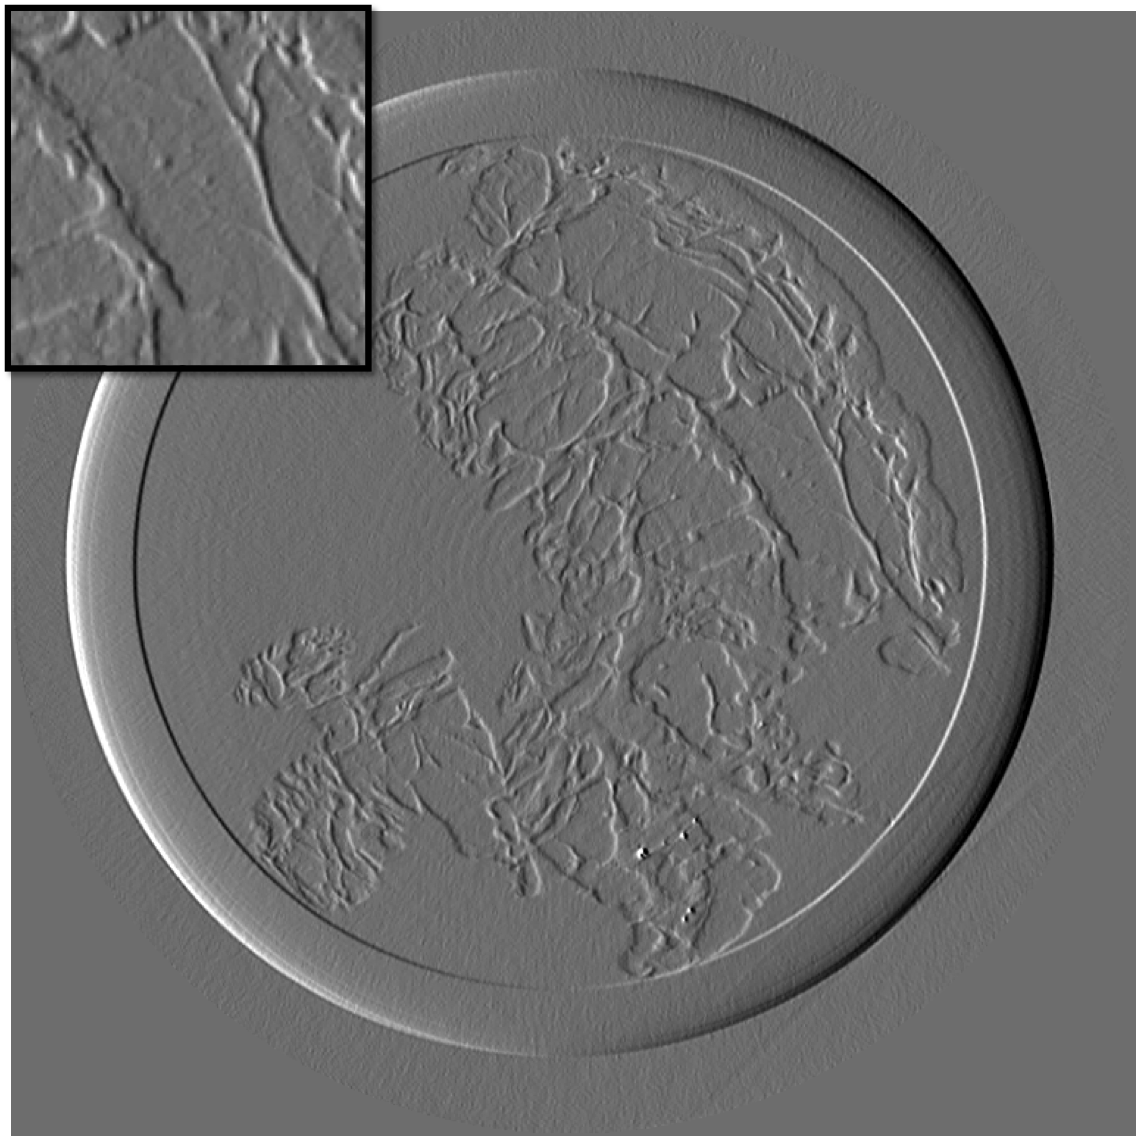

Figure 10 is the reconstruction for a pixels slice, using only 200 projections over the 1000 available. The upper left square is a zoom in the region marked in sub figure 10. The right column is the reconstruction with our method for X and Y components, while the left column is reconstructed with standard filtered back-projection using all 1000 available projections. Using our method we can still generate a high quality image with only one fifth of the projections which would be otherwise necessary to generate a high quality reconstruction with the standard FBP method. Visually the difference between the FBP results obtained with full data set and our method with a five-fold reduction of data is barely noticeable. The different borders of structures like skin layers, fatty tissues, and collagen strands are easily identified. The obtained result are very promising and a systematic evaluation for clinical application is under-way. The radiation dose absorbed by the sample during 200 projections is comparable to that of a standard clinical dual view (2D) mammography (3.5mGy).

For an eventual future clinical application of the PCI method it is important to investigate which is the acceptable compromise in terms of low dose and sufficient level of image quality. We need therefore to better explore how the quality of the reconstruction is degraded when we reduce the dose (i.e. number of projections and the acquisition time) further below the standard values. To this end, we performed a reconstruction with only 125 projections and results are shown in the figure III-D for one gradient differential image.

For an eventual future clinical application of the PCI method it is important to investigate which is the acceptable compromise in terms of low dose and sufficient level of image quality. We need therefore to better explore how the quality of the reconstruction is degraded when we reduce the dose (i.e. number of projections and the acquisition time) further below the standard values. To this end, we performed a reconstruction with only 125 projections and results are shown in the figure11. The first column present the result using our method, the second column is the result of reconstruction using FBP algorithm.

If a slightly higher noise level is tolerable, the method may be used with very few projections and thus applied to the screening and diagnosis of human breast cancers with an even lower radiation dose than conventional dual mammography. The results of our reconstruction show an image quality and a capability of discriminating fine structures that are still clinically acceptable. On the contrary, images produced with the standard FBP reconstruction method are very noisy and not diagnostically satisfactory.